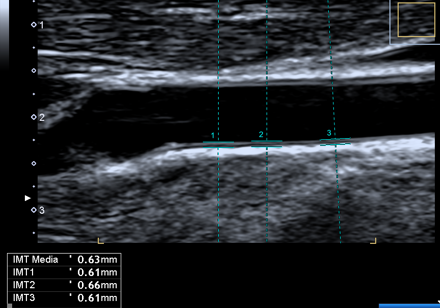

Riusciamo a “guardare” dentro le carotidi mediante un semplice esame non invasivo: l’ECOCOLORDOPPLER.

L’esame permette di valutare “la salute” delle nostre carotidi, le iniziali alterazioni della parete arteriosa (misurando l’ispessimento dello strato intermedio ed interno del vaso definito IMT), la presenza di placche ateromasiche e la % di restringimento del vaso.

Ecocolordoppler: misurazione IMT (spessore tra strato intermedio ed interno dell’arteria) | |

Studi scientifici hanno dimostrato l’importanza del ruolo dell’IMT dell’arteria carotide come iniziale marcatore per calcolare il rischio di patologie cardiovascolari. In particolare l’IMT risulta essere significativamente associato con il rischio d’infarto cardiaco, di ictus cerebrale, di morte improvvisa; tutto ciò anche in soggetti apparentemente sani con età superiore a 65 anni.